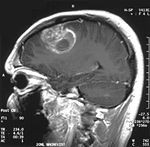

glioblastoma-agydaganat-d0000112A96af0a5dd288

A diklór-acetát (DCA) daganatellenes hatásának lényege , hogy a sejtek mitokondriális működésének helyreállítása révén újra működésbe lép a "programozott sejthalál", így a tumor nem növekszik, hanem összehúzódik, mérete csökken.

A kulcslépés tehát a daganatok anyagcseréjének megváltoztatása. A DCA klinikai tanulmányok szerint is a daganatnövekedés visszafordítására képes. A programozott sejthalál (apoptózis) miatt a rákos sejtek "elpusztítják önmagukat" anélkül, hogy bármiféle kárt tennének az egészséges sejtekben.